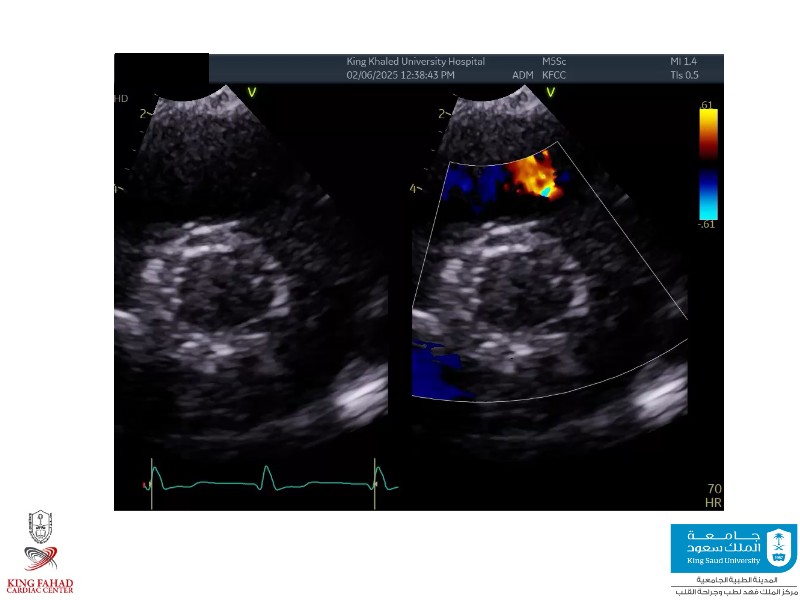

This session helps you anticipate and address complex scenarios such as mitral valve-in-valve, TAV-in-SAV, and valve-in-valve-in-valve procedures. Learn from expert case discussions that explore procedural strategies, technical challenges, and best practices to optimize outcomes in redo structural heart interventions.

- To anticipate and manage second valve scenarios with SAPIEN 3 Ultra RESILIA, including mitral valve-in-valve, TAV-in-SAV, and TAV-in-TAV

- To understand procedural strategies and challenges in complex redo scenarios using SAPIEN 3 Ultra RESILIA